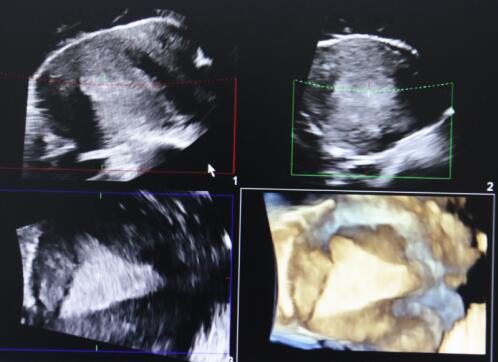

“火眼金睛”的超声神探——飞利浦EPIQ7四维彩超机

世界领先的飞利浦EPIQ7高端四维彩超机目前已经落户建平县医院,该设备采用全球先进的矩阵全景容积成像系统,能够直观、立体显示人体器官的三维结构及动态4D超声技术,它的投入使用极大地提高了我院妇科、产科、儿科、消化系统、泌尿系统、血管、小器官、腹部等各种疑难疾病的诊断准确性和治疗水平。其动态实时立体成像,材质纯净,超低声能及声噪输出的电子纯净波矩阵四维探头,更是代表着当今世界超声领域的最前沿。

四维彩超在产科的主要作用就是排查畸形,它通过表面成像、透明成像、骨骼成像等多种成像方式,准确、清晰、直观地观察所看部位及脏器。在胎儿检查过程中,实时动态不仅可以观察胎儿在母体里打哈欠、伸懒腰、吸吮手指等奇妙的动作,更为重要的是能够全方位,多角度地观察宫内胎儿的生长发育情况,为早期诊断胎儿先天性畸形,如唇裂、脊柱裂、颅脑发育异常、骨骼发育异常、心血管畸形等提供准确的科学依据。

胎儿四维图像